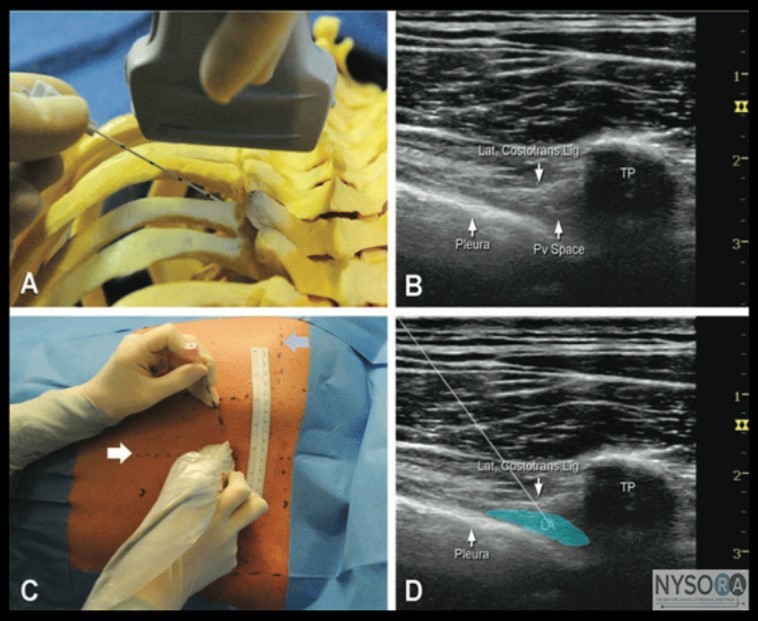

We must know that, Thoracic epidural and paravertebralblocks became the gold standard techniques to achieve this goal, but not every anesthesiologist is comfortable performing these procedures (Figure 4) 45.

Figure 4.U/S guided Thoracic epidural and paravertebral blocks 43